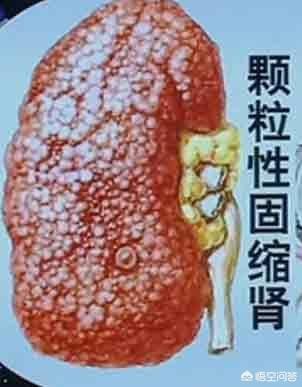

L'hypertension à long terme, si elle n'est pas contrôlée, peut conduire à l'athérosclérose des petites artères rénales, à l'hypoplasie rénale, à l'hypoplasie rénale, à une nouvelle augmentation de la pression artérielle, ce qui entraîne un cercle vicieux, et finalement, la fonction rénale continue à se détériorer, devenant une urémie.

L'hypertension artérielle peut également entraîner une atrophie des reins.

Les reins normaux sont ronds et pleins, et l'hypertension artérielle à long terme entraîne un rétrécissement des reins des patients, avec une surface granuleuse et une diminution de la fonction rénale.